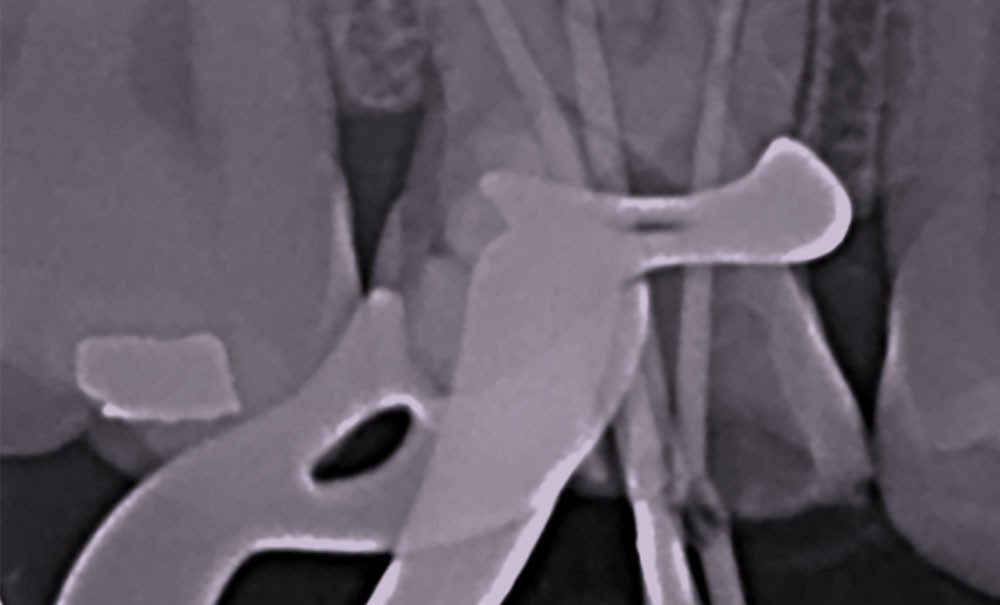

Perforation supra-osseuse (fig. 1)

Les perforations supra-crestales sont la plupart du temps iatrogéniques et surviennent lors de la réalisation de la cavité d’accès, ou de la recherche des entrées canalaires. Il s’agit généralement d’une communication avec un diamètre bien défini et aux contours nets. De ce fait, ce type de perforation est appelée « perforation à quatre parois ». Les perforations peuvent également être d’origine pathologique (résorption cervicale externe, carie active).